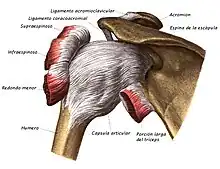

Ilustración de una articulación sinovial (diartrosis). | ||

Los huesos se enlazan mediante articulaciones que permiten el movimiento, existen diferentes tipos de articulaciones, pero una de las más importantes son las articulaciones sinoviales, representada entre otras por la cadera, rodilla, hombro y articulaciones interfalángicas de manos y pies. Tienen gran movilidad y están formadas por una cavidad llena de líquido sinovial y tapizada por la membrana sinovial. Los extremos de los huesos que la forman están recubiertos por cartílago articular. Todo el conjunto se refuerza exteriormente mediante una cápsula articular fibrosa que le da mayor estabilidad.[1][2]

Desempeña un papel muy importante en las articulaciones sinoviales como la rodilla y el hombro, está constituido por cartílago hialino y recubre la superficie de los huesos, siendo su espesor entre 2 y 4 mm. Tiene la función de transmitir y amortiguar las cargas y proporcionar una superficie adecuada para el deslizamiento de las superficies articulares. No tiene vasos sanguíneos propios, por lo que las sustancias nutritivas le llegan a través del líquido sinovial. La capacidad de regeneración si sufre lesiones o desgaste por sobrecarga es escasa.[5] Está compuesto por células especiales llamadas condrocitos rodeados de matriz extracelular. La matriz extracelular está formada por agua (65-80 %), colágeno (10-20 %) y proteoglicanos (10-15 %) que le otorga resistencia a las fuerzas de compresión. Los condrocitos son las encargadas de producir los componentes estructurales que forman el cartílago.[5][6]

Cápsula articular

La cápsula articular es una estructura formada por tejido conectivo denso que rodea la articulación y le da estabilidad, firmeza y flexibilidad, uniéndose estrechamente a los extremos del hueso. En el interior de la cápsula articular se encuentra el líquido sinovial.

- Articulaciones esféricas o enartrosis: tienen forma de bola y receptáculo y se caracterizan por el libre movimiento en cualquier dirección, por ejemplo, la coxofemoral (cadera) y la escapulohumeral (hombro). Permiten los movimientos en más de 3 ejes o planos (multiaxiales) y hacen posible los movimientos de abducción, aducción, flexión, extensión, rotación interna y rotación externa.

El término diartrosis procede del griego día, separación, y arthron, articulación. Son las más numerosas en el esqueleto. Se caracterizan por la diversidad y amplitud de los movimientos que permiten a los huesos. Poseen cartílago articular o de revestimiento en ambas partes de la articulación. Un ejemplo típico de diartrosis es la articulación glenohumeral, la articulación que une el húmero con la escápula. En el contorno de la cavidad glenoidea se halla el rodete marginal o rodete glenoideo. Las dos superficies articulares están unidas por la cápsula que se fija alrededor de la cavidad glenoidea de la escápula y del cuello anatómico del húmero. La cápsula está reforzada exteriormente por ligamentos extracapsulares e interiormente está tapizada por la sinovial. Son las más móviles y frágiles ya que son menos resistentes y más recubiertas.[8]